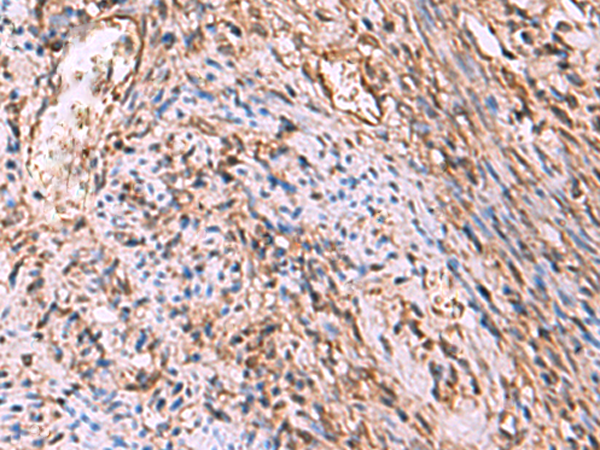

IHC positive control:

Human tonsil and Human cervical cancer

IHC Recommend dilution:

50-300